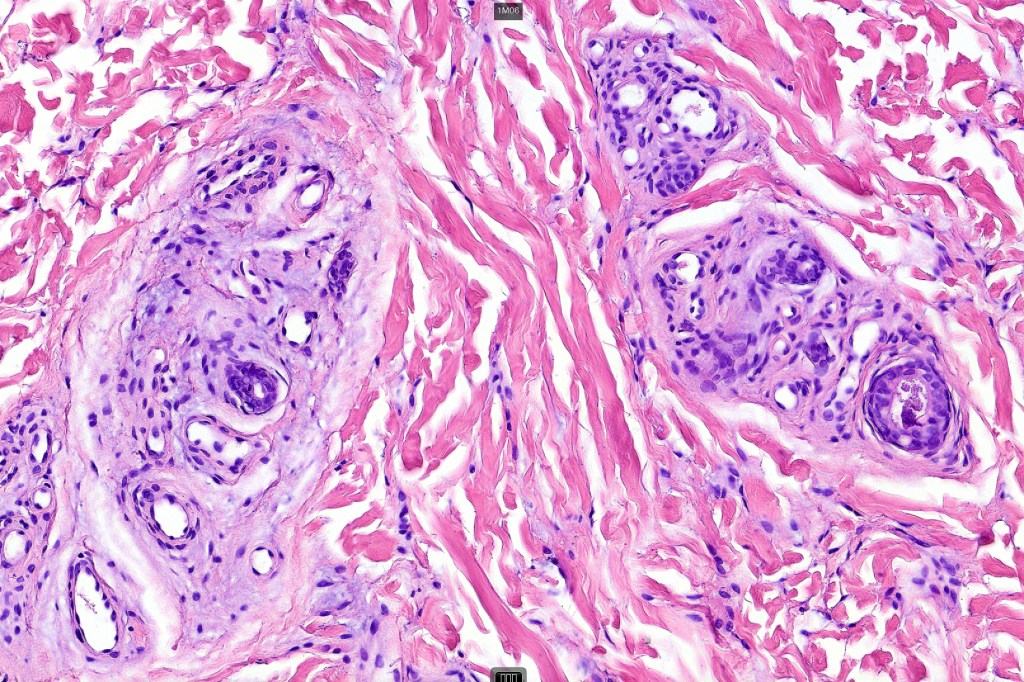

Histological features

•Mid- to deep dermal lobular infiltrate of sweat glands & ducts accompanied by capillaries & small vessels

•Variable adipose, smooth muscle, neural & apocrine components